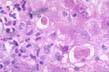

Fig.127 - Positive immunoperoxidase reaction for HDV antigen. Nuclear localization. |